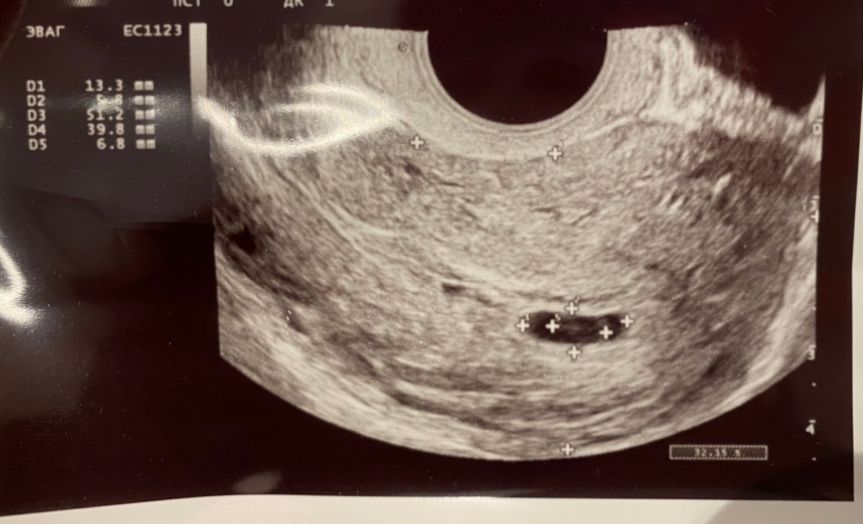

Ивс, я по этой же таблице смотрела что рост нормальный в калькуляторе. Но за эту неделю у меня ноль развития эмбриона. По узи видно что желточный вырос в три раза, а эмбрион куда то рассосался, сб опять же как не было так и нет. Всё относительно и по таблицам у меня все как будто бы хорошо, но по факту нет 🤷‍♀️

Доктор правильно сказал- под вопросом. Только в динамике смогут точно сказать. УЗИ через неделю и станет ясно. У меня ещё и мазало, и то никто сразу на прерывание не отправил, дали шанс и поддержку. И Вы пока займите выжидательную позицию, ещё ничего не ясно. Залезла в свои записи. 7и3: ПЯ 13*11, ЖМ 3,2, КТР 2, СБ-?. МА. Но это не показатель.

Настюшка, у вас жм 3.2. А мой за недель вырос с 2 до 6.4. Это считается очень плохим знаком…когда эмбрион не растёт а мешочек растёт ударным темпом

У меня было 2 зб. Первая в 6 недель на узи всё идеально, но в 9 сб не нашли. Вторая хгч изначально плохо рос, еле удваивался, по узи отставал на неделю, потом на две... В 6 недель ПЯ 6 мм, в 7 ПЯ 8 мм. Почти не росло, оставляли до последнего, пока через транексам не пошли М.